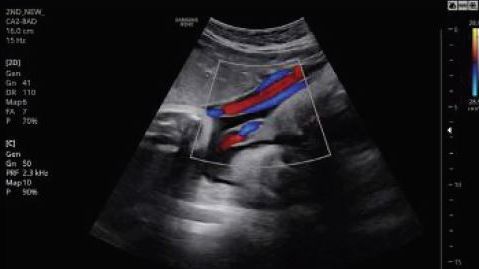

A magzaton a következő testrészek és szervek vizsgálhatóak ebben az időszakban: az állcsont-állkapocs, kialakulóban a rekesz és a tüdő, látható a szívbillentyűk mozgása, a véráramlás, az orrcsont, a vesék, a húgyhólyag és a gyomor. Vizsgálható a méhlepény tapadása és a köldökzsinór állapota is, hogy rendesen fejlődik-e a törzs és a végtagok, valamint, hogy elegendőnek tűnik-e a magzatvíz mennyisége.